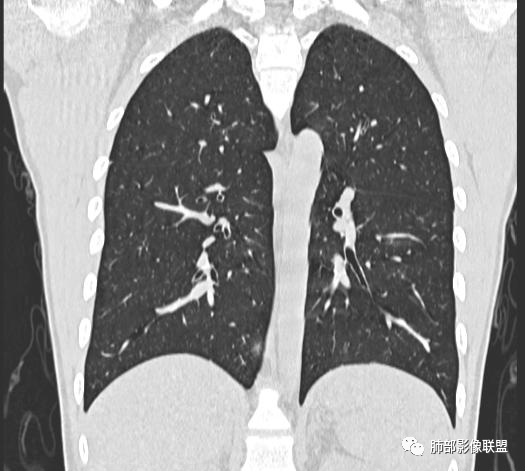

小强:青年,发热,皮疹;双肺散在结节,周围磨玻璃,点晕征,疱疹病毒感染,鉴别荚膜组织胞浆菌,结核。 大雄:青年,急性起病,发热伴全身皮疹2天,抗病毒治疗体温有下降。双肺随机分布大小不等类圆结节,“点晕征”。考虑水痘-疱疹病毒(VZV)血播询问接触史,查体皮疹分布以及形态基本可诊断。 王开金江津中心医院呼吸科:青年男性,起病急,病程短,以发热,皮疹为首发症状,感染指标以单核细胞升高为主,胸部ct双肺多发结界,周围有晕,点晕表现,随机分布,同意於老师意见,水痘疱疹病毒血流感染累及肺。 王秀仙:双肺多发大小不等结节,周围有晕,边缘模糊,呈点晕征表现。青年,急性起病,发热伴全身皮疹2天,抗病毒治疗体温有下降。考虑疱疹病毒。鉴别荚膜组织胞浆菌。 傅昌瑜:19岁男性,发热、全身皮疹2天,单核细胞增高,双肺多发结节,结节边缘见边界不清磨玻璃影。点晕征+发热、全身皮疹+单核细胞增高——考虑水痘-带状疱疹病毒肺炎。 一切∮随缘:年轻男性,发热,皮疹两天,实验室,CRP,PCT增高,影像:双肺多发散在磨玻璃结节,边界欠清,大小不等,呈点晕征改变,以血管束周围分布为主,局部血管束略增粗,其它无明显改变,考虑:1:病毒性肺炎(水痘疱疹病毒?不知道皮肤有无改变)2:真菌(组织胞浆菌,血管侵袭性肺曲霉)3:GPA4:寄生虫(实验室没有看到嗜酸细胞增高) 赵山河:双肺散在结节,周围有晕,边缘模糊,呈点晕征表现。青年,急性起病,发热伴全身皮疹2天,抗病毒治疗体温有下降。考虑水痘—疱疹病毒感染。洪桥爱:青年男性,发热、皮疹2天,伴瘙痒,皮疹于面部首发,之后进展至全身,虽然没有对皮疹进行描述,但是从出疹时间及皮疹进展情况,伴瘙痒,应该就是个水痘患者;CT提示双肺随机分布结节影,部分结节伴有边界不清晕征,考虑水痘血播肺。 刘强:年轻男性,急性起病,皮疹,发热,抗感染治疗体温下降,说明有效。影像表现为散在点晕征,感染类疾病谱(疱疹病毒,真菌,结核),结合年龄,皮肤皮疹,考虑水痘-疱疹病毒性肺炎。 小兜:男性,19岁,发热皮疹两天,颜面部至全身,CRP,降钙素及单核增高。CT示双肺散在小结节,周围伴磨玻璃影,点晕征,考虑为水痘-带状疱疹病毒(varicella-zoster virus,VZV)肺炎 必有路:青年,皮疹+发热+“点晕征”→水痘-疱疹病毒(VZV) 许慧良:青年男性患者,发热、皮疹2天,体温最高38.5℃,第3天皮疹扩展至全身,伴瘙痒,胸部CT:双肺多发随机分布的小结节,结节周边见边界模糊的晕征,考虑水痘病毒感染流心明智:男,19,急性起病,发热伴全身皮疹2天。出疹顺序头→全身,抗病毒有效。胸部CT:两肺多发大小不等类圆形实性小结节影,随机分布,结节周围环绕GGO,边界模糊,呈点晕征。出疹特点是关键,未提示。考虑:血播病毒性肺炎,水痘-疱疹病毒?麻疹?鉴别荚膜组织胞浆菌、TB、血管炎、寄生虫等。 浪迹天涯:病灶多为5-10mm大小结节,结节周围可见磨玻璃样的晕环,常多发,可分布于肺内任何区域,考虑水痘—带状疱疹病肺炎如果短时间内有新的一个区域浸润,更加能说明,